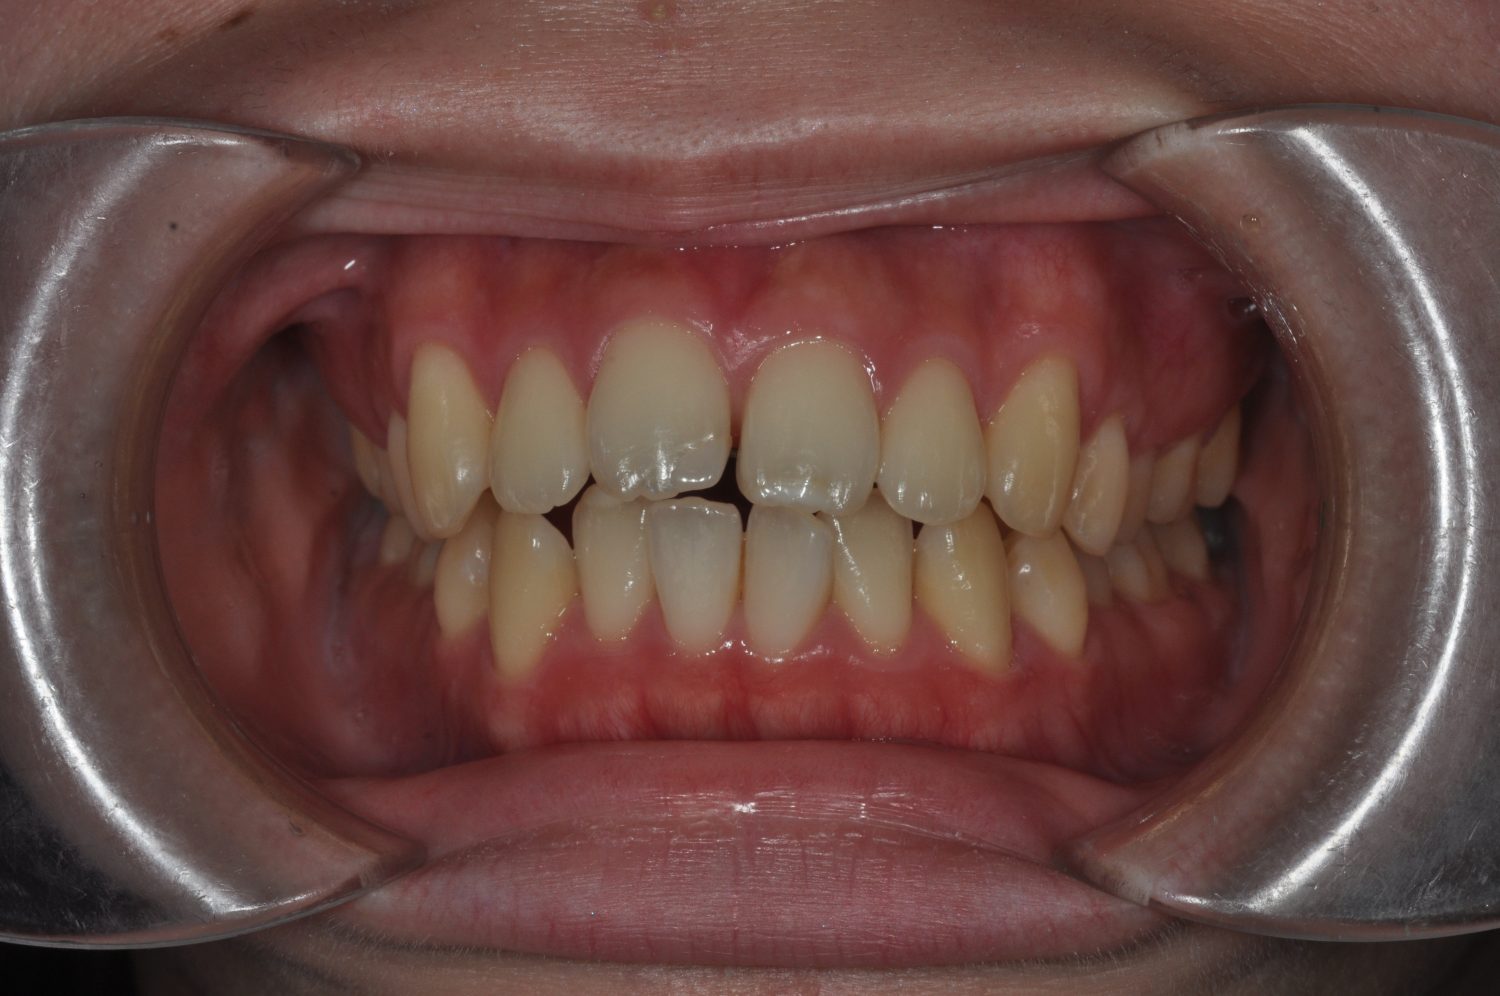

| 主訴 | 口唇の突出感 |

| 治療内容 | 小臼歯抜歯によるマルチブラケット治療 |

| 治療費 | Ⅱ期治療料金:330,000円(税込) 調整料 5,500円(税込)×19回 保定時:22,000円(税込) 計 456,500円(税込) |

| 治療期間 | 1年7ヶ月 |

| 治療回数 | 21回 |

| 想定されたリスク | 矯正後、後戻りする可能性がありました。また、歯根吸収や歯肉退縮のリスクがありました。 |